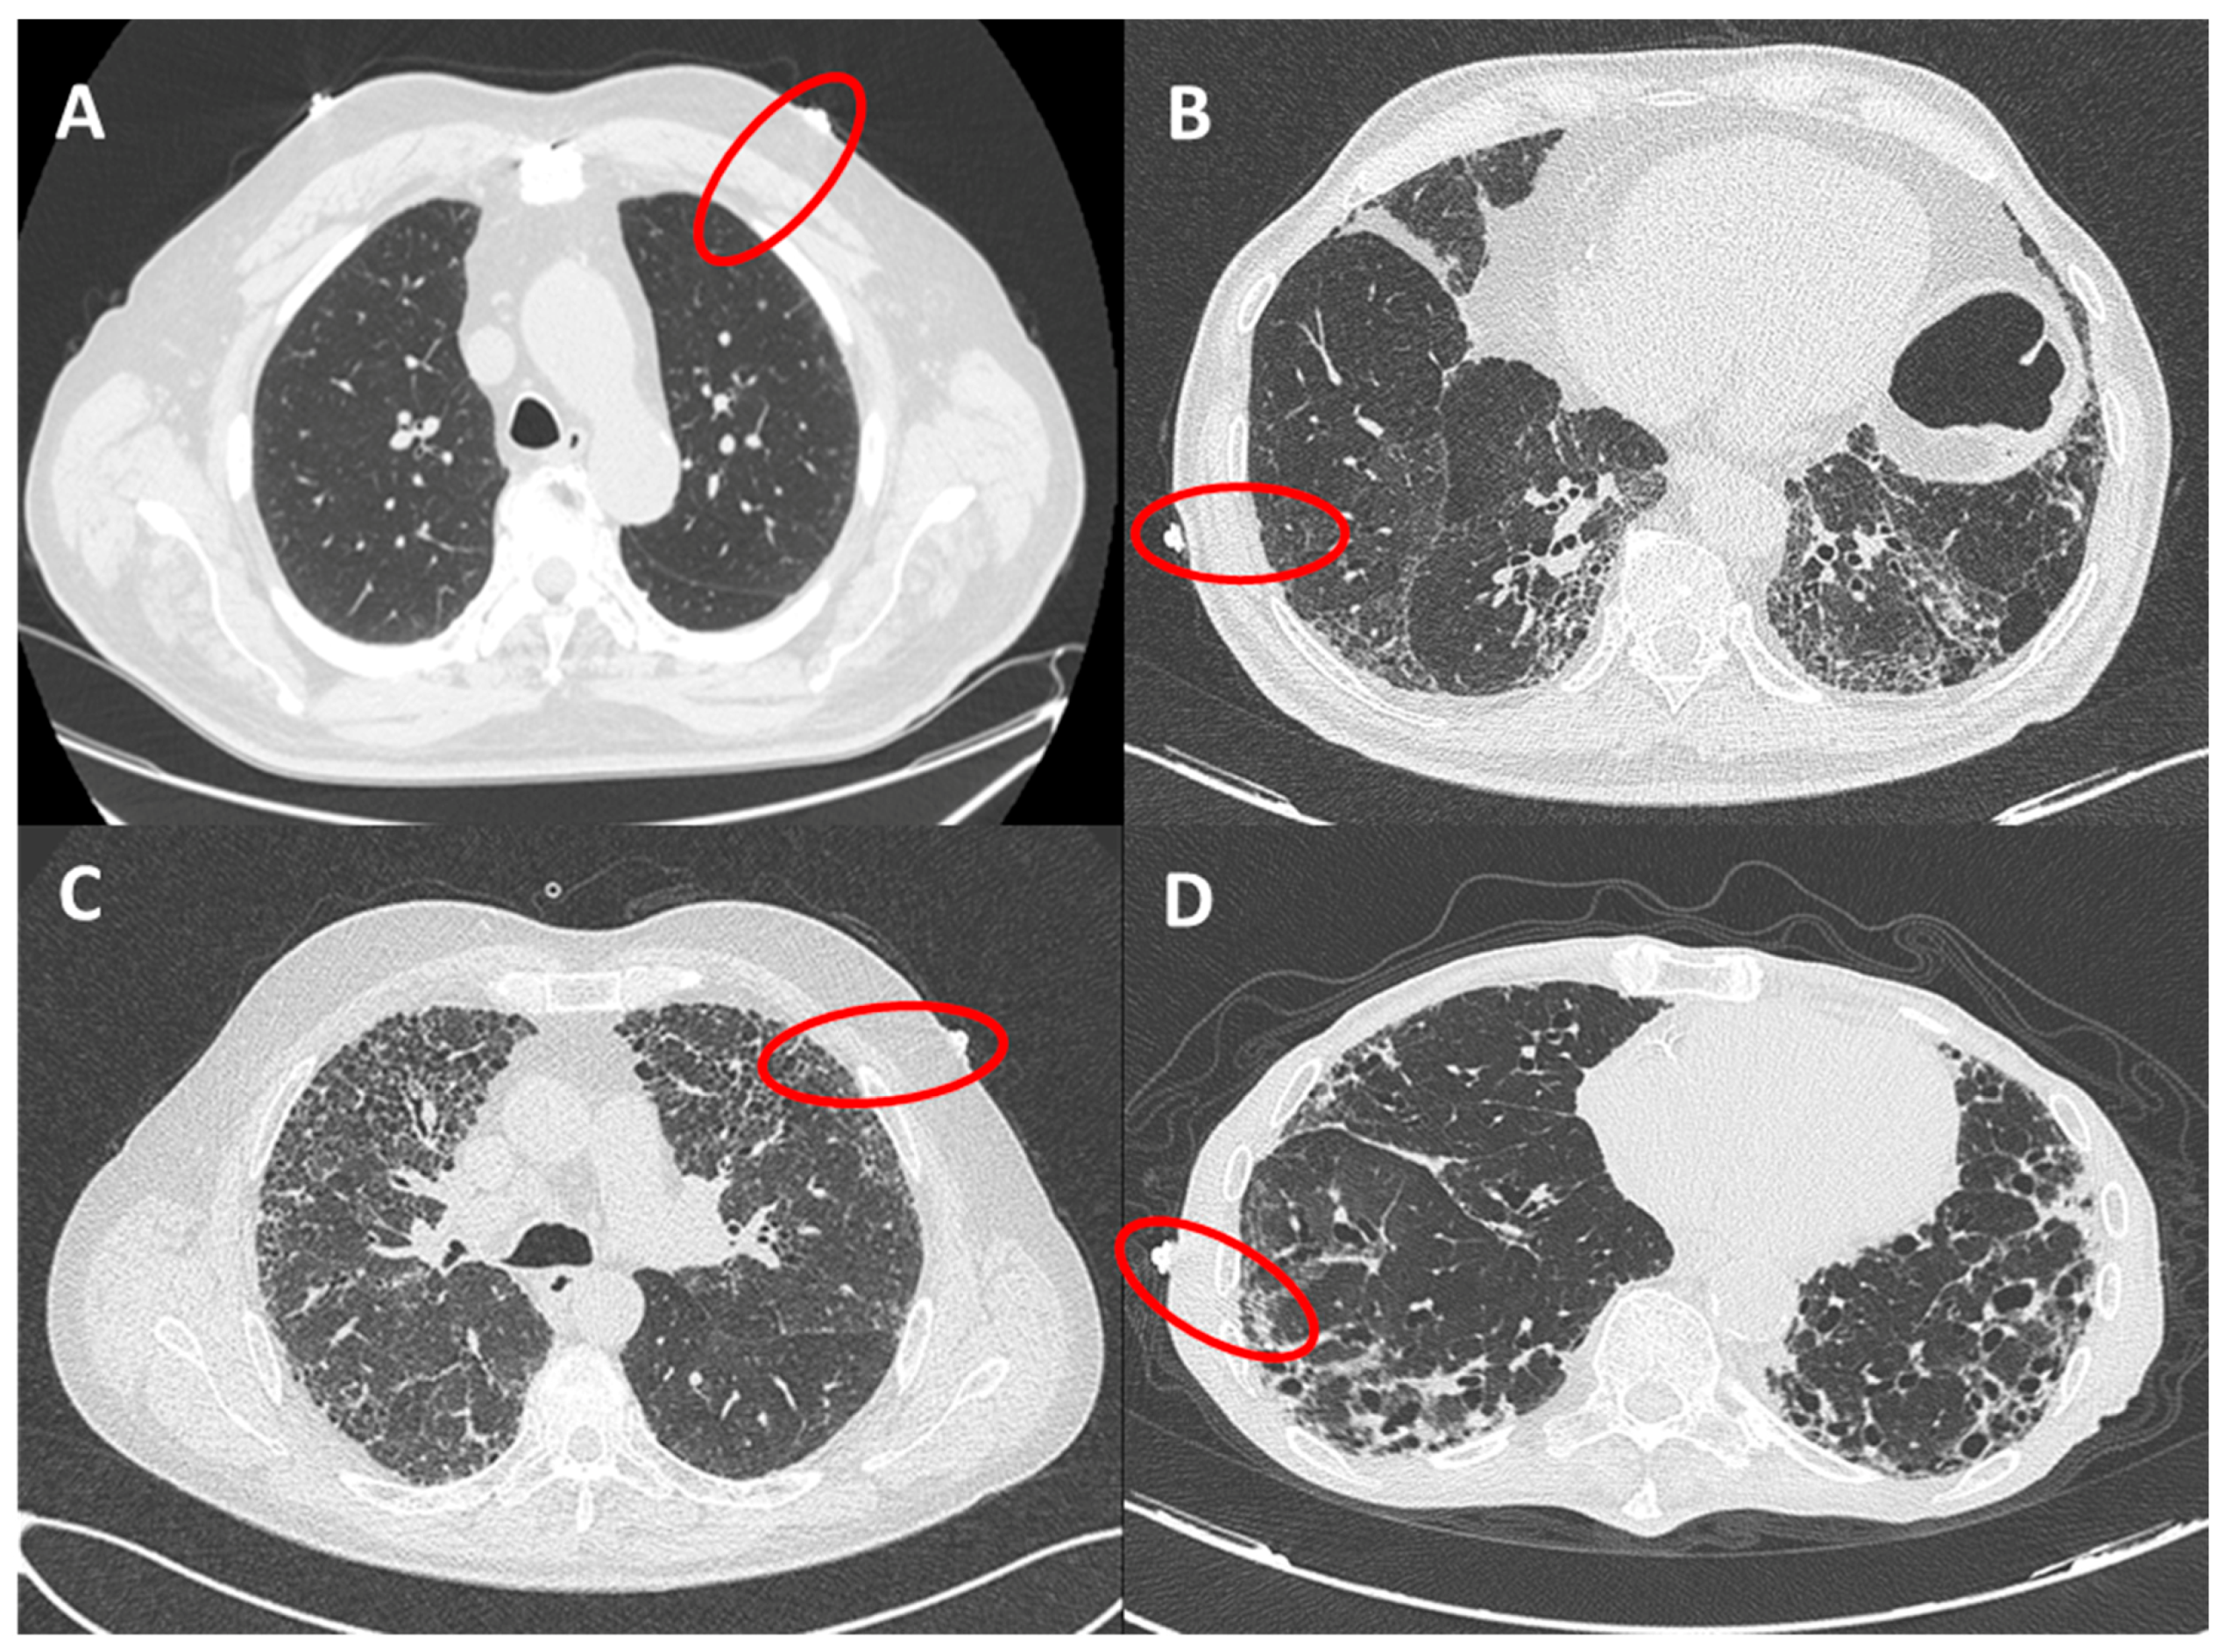

The presence of fibrotic infiltrates on HRCT was evaluated and contemporaneously graded by 2 radiologists (ARL and LC), with expertise in fibrotic interstitial diseases. The analysis was performed only on peripheral lung (within 2 cm in depth from visceral pleura and corresponding to dimension of secondary lobule) and reported as grade 1 (from 0% to 10% of fibrotic changes, mild alterations), grade 2 (10%–50%, moderate), grade 3 (50%–90% severe) and grade 4 (90%–100%, massive fibrotic subversion or honeycomb) (Figure 2). A concordant HRCT score was provided.

Figure 2. HRCT grades related to red circles showing landmarks of ultrasound assessment. (A): grade 1 (from 0 to 10% of fibrotic changes, mild alterations); (B): grade 2 (10–50%, moderate); (C): grade 3 (50–90% severe); (D): grade 4 (90–100%, massive fibrotic subversion or honeycomb).